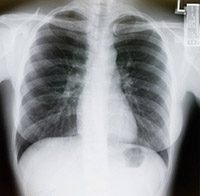

Lung cancer screening for smokers moves toward standard of care

When a massive clinical trial about lung cancer screening shows a benefit to current and former smokers, why can it take so long to become...